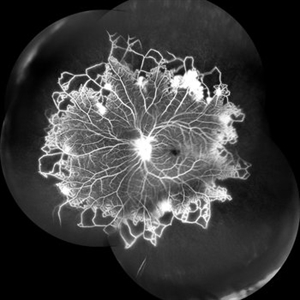

Retinitis Pigmentosa With Hemangioma CF

Dec 15 2016 by Manish Nagpal, MD, FRCS (UK), FASRS

Fluorescein angiography OS of a patient having retinitis pigmentosa with a hemangioma inferiorly.

Condition/keywords: hemangioma, retinitis pigmentosa